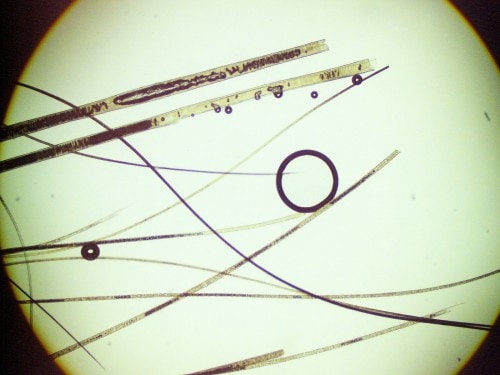

Les données épidémiologiques, cliniques et l’absence d’antécédents médicaux rendent peu probable l’hypothèse d’un état hypersensible. Des raclages permettent d’exclure une démodécie. La culture fongique est refusée par la propriétaire et cet examen est reporté ultérieurement selon l’évolution. La trichoscopie montre des poils cassés et en « mikado », confirmant le caractère auto-induit (léchage, mordillement par le chat lui-même) (cf. photo 4). La cytologie (calques cutanés sur les lésions érythémateuses, croûteuses et suintante) révèle la présence de rares polynucléaires neutrophiles majoritairement dégénérés et de rares bactéries de type cocci en position extra et intracellulaire (phagocytose) confirmant l’hypothèse d’une pyodermite superficielle bactérienne modérée.

Photo 4 : Trichoscopie : noter les tiges pilaires cassées en « bois vert » et en mikado, traduisant un comportement de léchage et/ou de mordillement